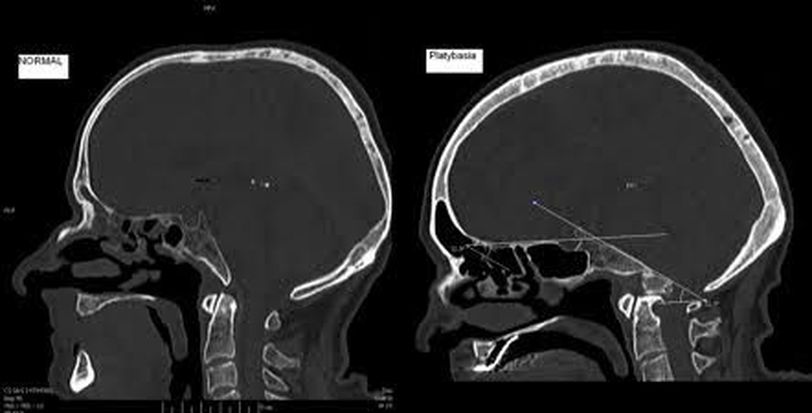

Platybasia is characterized by flattening of the skull base and a skull angle- the angle between anterior base of skull and clivus- is over 140°. In platybasia, the floor of the posterior cranial fossa buldges upward. The upper cervical vertebrae may be displaced superiorly and brainstem might be impimged leading to neural deficits. It can be congenital or aquired. Aquired causes include pagets disease, osteomalacia, rickets, trauma etc. Congential causes include achondroplasia, down's syndrome, osteogenesis imperfecta, craniocleidodysostosis etc. Image via: https://images.app.goo.gl/Vx1AdRgYm7ozZmy46